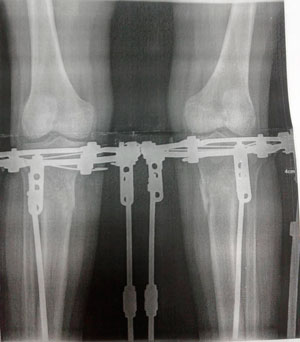

Исходник - 34 года.

Дата операции -- 03.07.2020